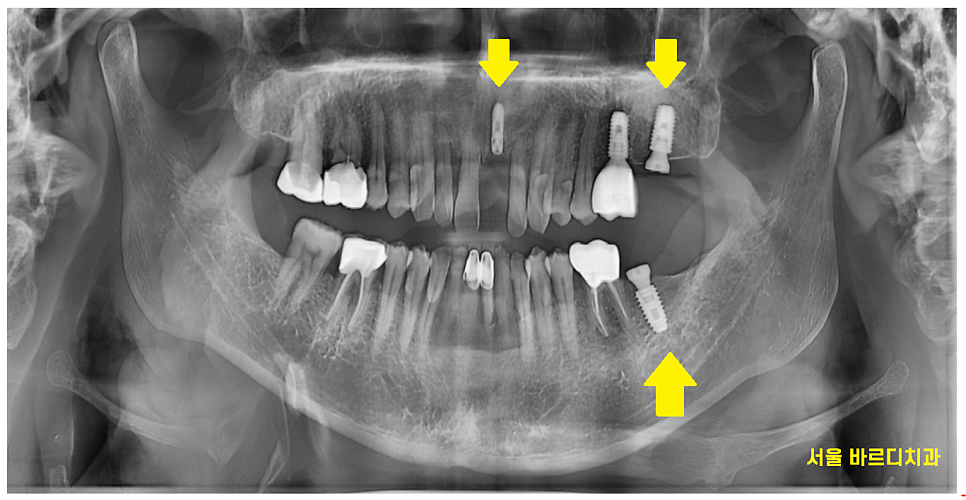

오른쪽은 치아 개수가 모두 있는 환자분

왼쪽은 위 아래 어금니 1개씩 사이좋게 없었습니다.

230622

환자분이 턱 뼈가 발달된 것을 보니

씹는 힘이 좋으신 환자분입니다~